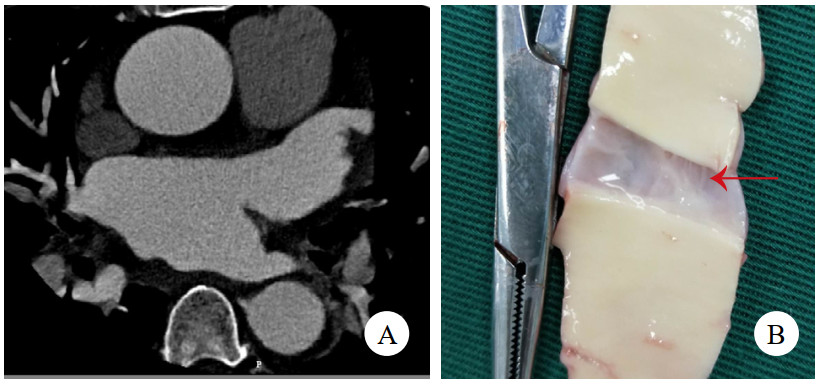

病例1,女,41岁,因“突发严重胸闷气促15 h”入院。发病后立即就诊于附近医院,查胸腹平扫CT提示急性肺水肿、双侧胸腔积液、心包积液,查血红细胞计数3.38×1012/L,肌酐369 μmol/L,乳酸11.7 mmol/L,钠尿肽超过检测上限,立即转诊至本院。考虑存在急性多脏器衰竭,立即收入重症监护室,因少尿予连续肾脏替代治疗。右侧胸腔穿刺引流液红细胞计数高达0.22×1012/L。床边经胸超声心动图(transthoracic echocardiography, TTE)未见主动脉病变,但见左心室弥漫肥厚符合高血压性心脏病,心包大量积液伴血块,且出现心包填塞,紧急行心包穿刺,但置管后引流不畅。因心包积液病因不明,且回顾前平扫CT可见升主动脉壁局部密度增高(图 1A),急查主动脉CTA,但影像科对升主动脉根部管壁褶皱情况考虑为搏动伪影。后查经食管超声心动图(transesophageal echocardiography, TEE),清晰可见升主动脉直径38 mm,距主动脉瓣环约16 mm处有飘动纤细光带,考虑升主动脉LIT(图 1B图 1C)。遂行急诊开胸手术,术中见心包腔内大量积血并血块,升主动脉外膜血肿延入肺动脉外膜至右侧肺门。建立体外循环后,在头臂干开口近侧阻断升主动脉,顺行灌注心脏停搏液良好,纵行切开升主动脉,见左右冠瓣上方横行内膜裂口,中膜无假腔形成,冠状动脉开口、主动脉瓣无病变。用26 mm人工血管置换升主动脉,手术顺利。术后复查TTE见人工血管通畅、形态良好。回顾并重建术前主动脉CTA,曲面重建可见内膜片(图 1D),该处主动脉直径为37 mm。患者术后肾功能衰竭持续,规律随访血透,6个月后失访。

注:A为平扫CT,箭头示升主动脉壁增厚、密度增高;B为TEE舒张期,箭头示飘动纤细光带;C为TEE收缩期,箭头示飘动纤细光带;D为主动脉CTA,曲面重建,箭头示内膜片 图 1 例1患者两次CT及术前TEE影像